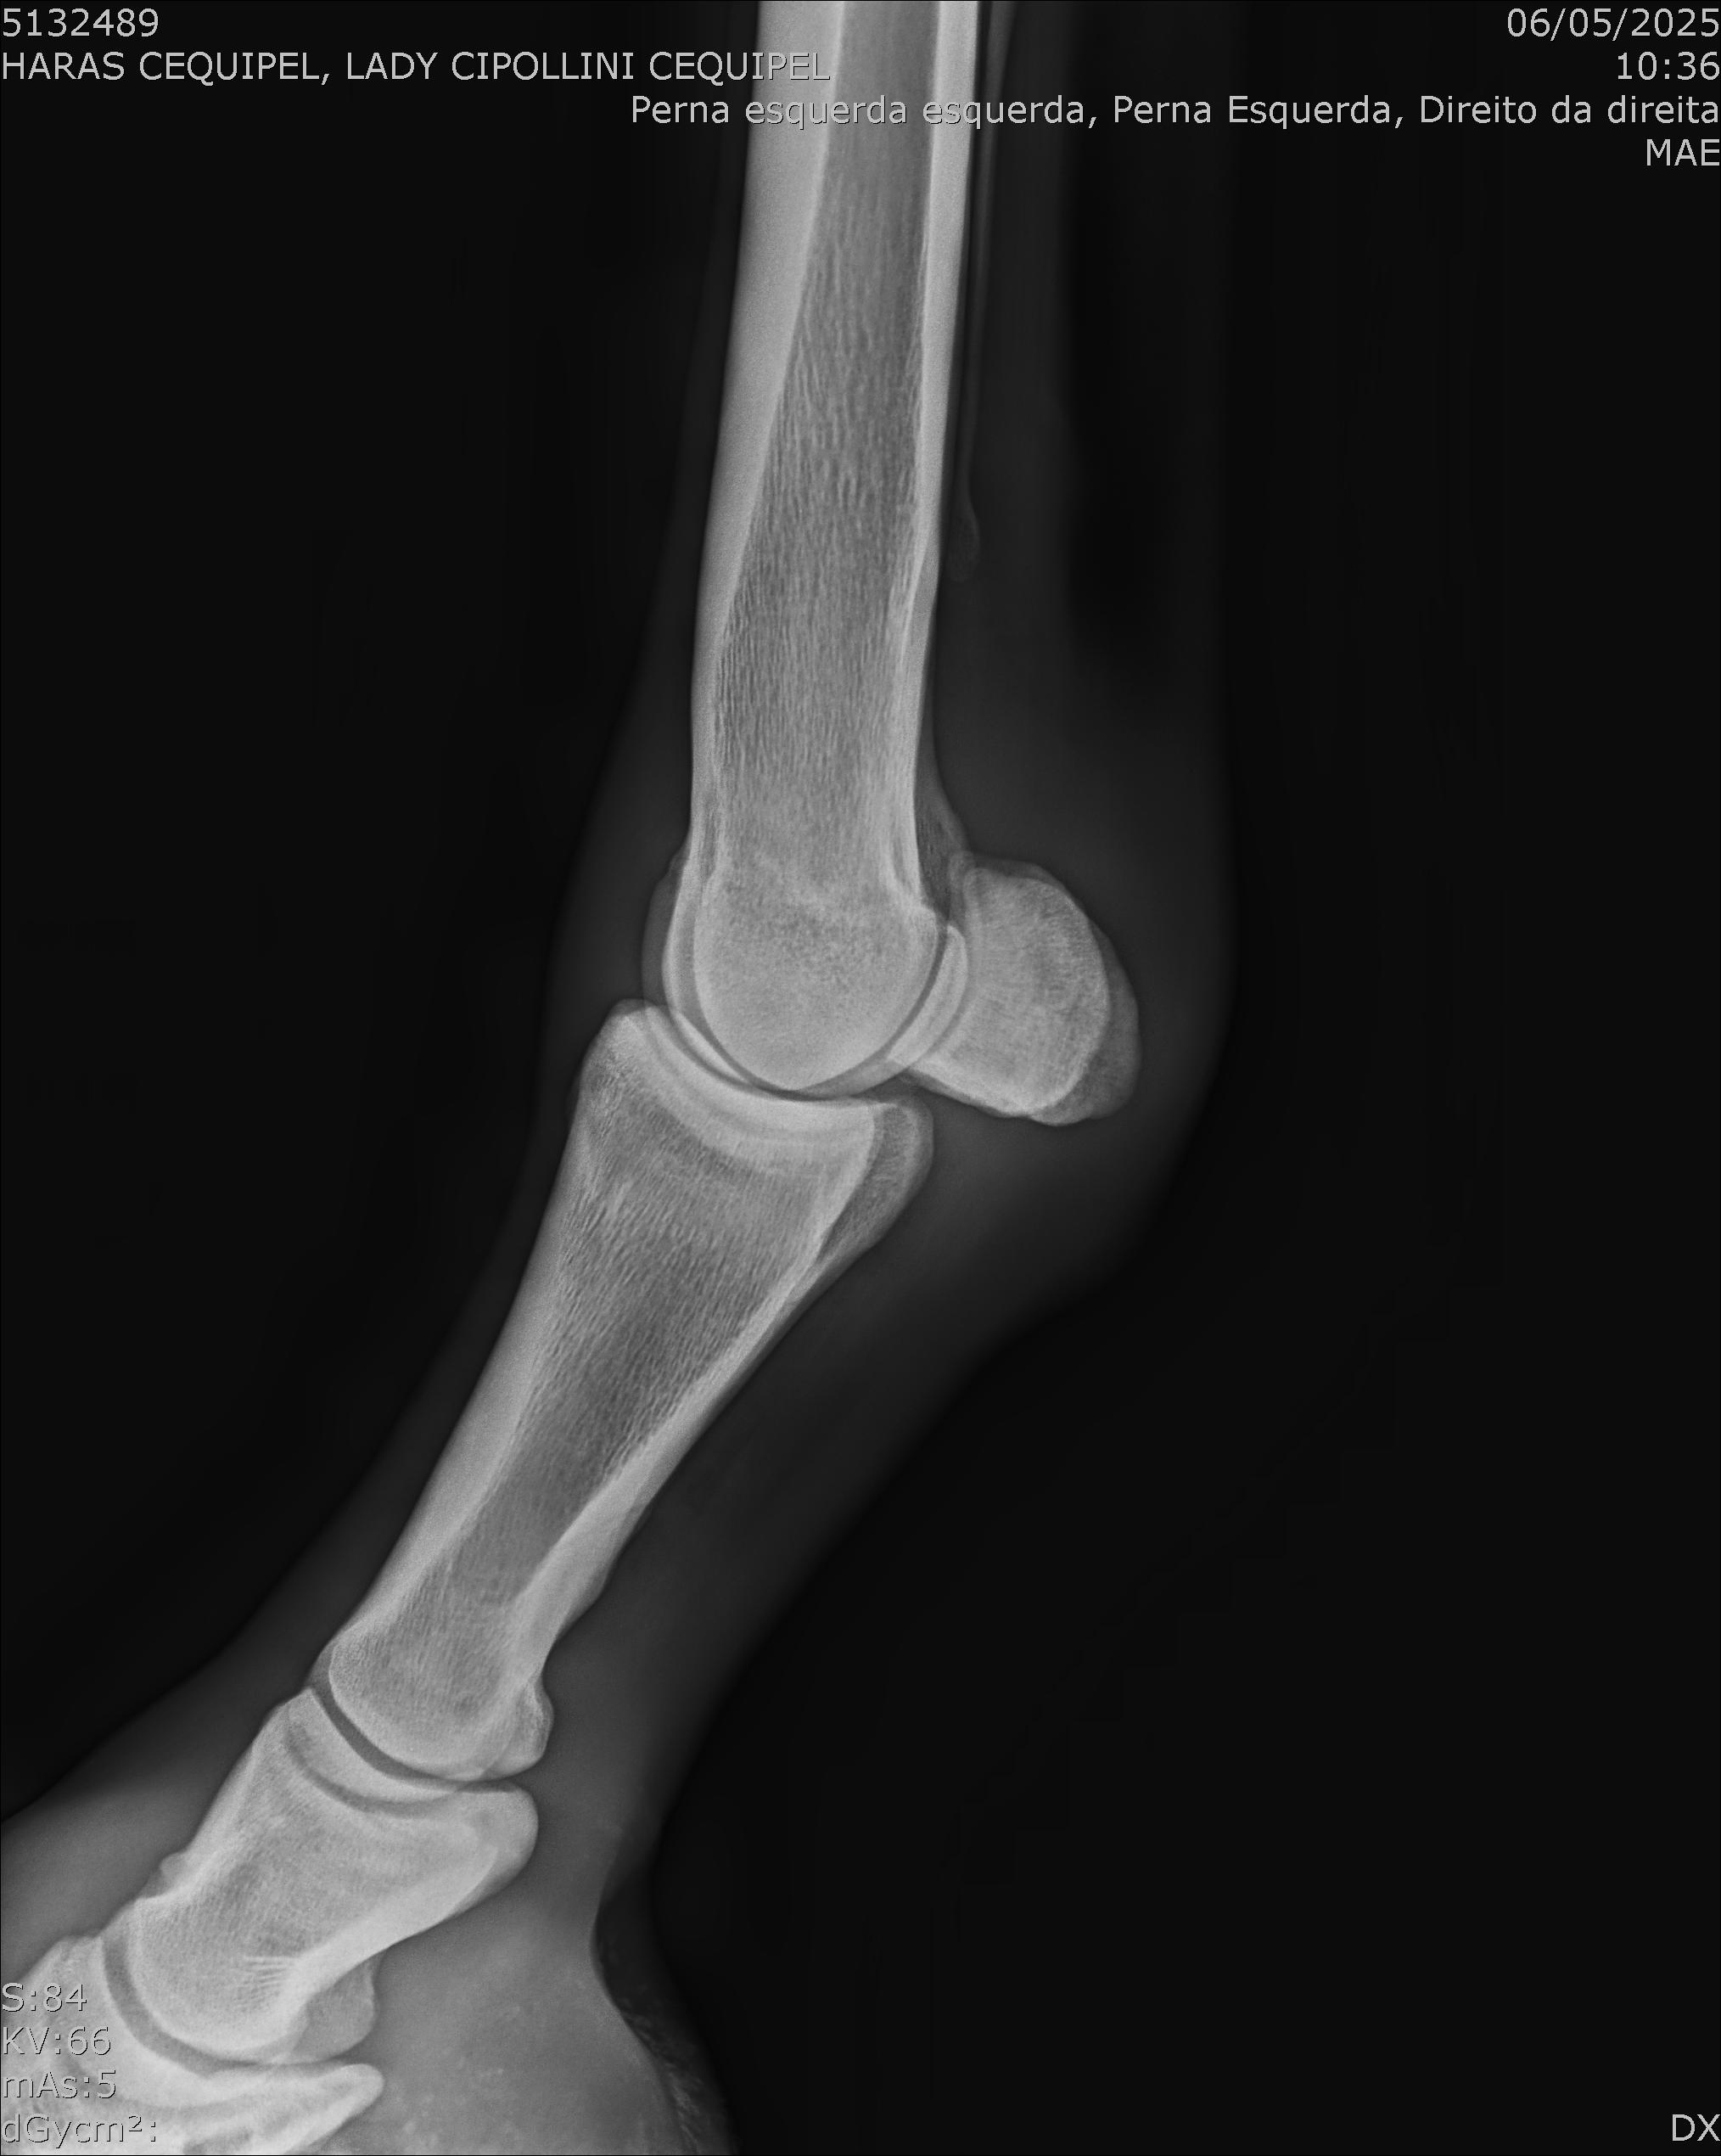

:: RAIOS-X DO LOTE